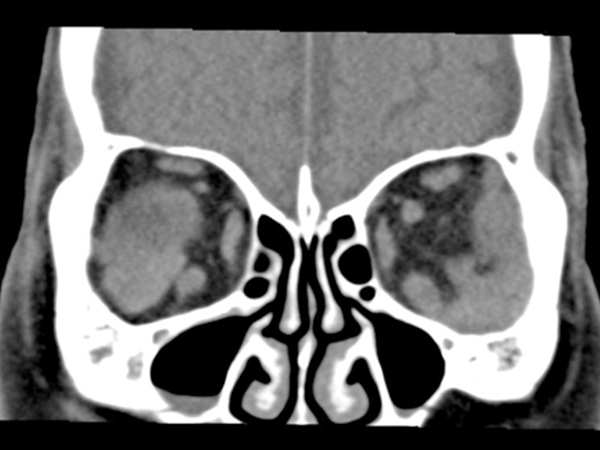

眼周囲(結膜、眼瞼、眼窩)に発生する悪性リンパ腫の多くは低悪性度MALTリンパ腫ですが、時に高悪性度のマントル細胞リンパ腫や、びまん性大細胞Bリンパ腫が発生します。診断は、造影CT、造影MRI、PET-CTを行い、確定診断のために部分生検を行います。治療は、組織型や病気に応じて放射線治療、全身化学療法を行います。

- 乳幼児の眼内に白色の腫瘤があれば多くの場合、網膜芽細胞腫です。視力障害、斜視などが症状として現れることもあります。診断はCT、造影CT,造影MRI、眼内液NSE測定で行い、通常生検は行いません。治療は、腫瘍が大きい場合や眼内に散布している場合は眼球摘出を行います。眼球保存を行う場合、また眼球摘出後に視神経浸潤や脈絡膜浸潤があった場合には、全身化学療法を行います。眼球保存療法では化学療法と併用して経瞳孔温熱療法(赤外線レーザー治療)を行います。